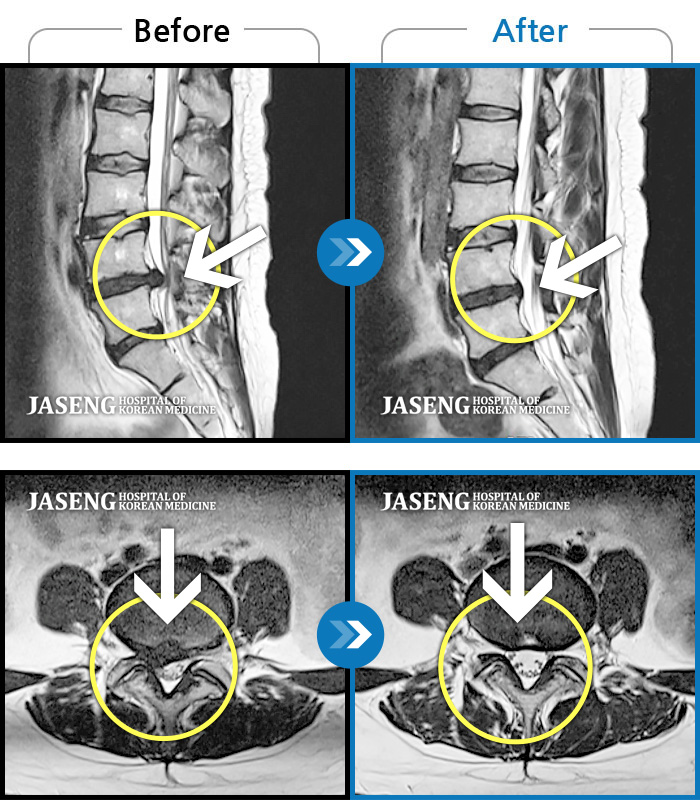

Before

After

환자에게 사전 동의를 받아 동일 조건에서 촬영되었습니다.

개인에 따라 치료 후 부작용이 발생할 수 있으니 의료진과 상담 후 치료를 진행하시기 바랍니다.

하부요추와 좌측 하지 후면 통증, 좌측하지 감각저하, 근력저하

좌측 하지 및 골반 방사통 및 저림증상